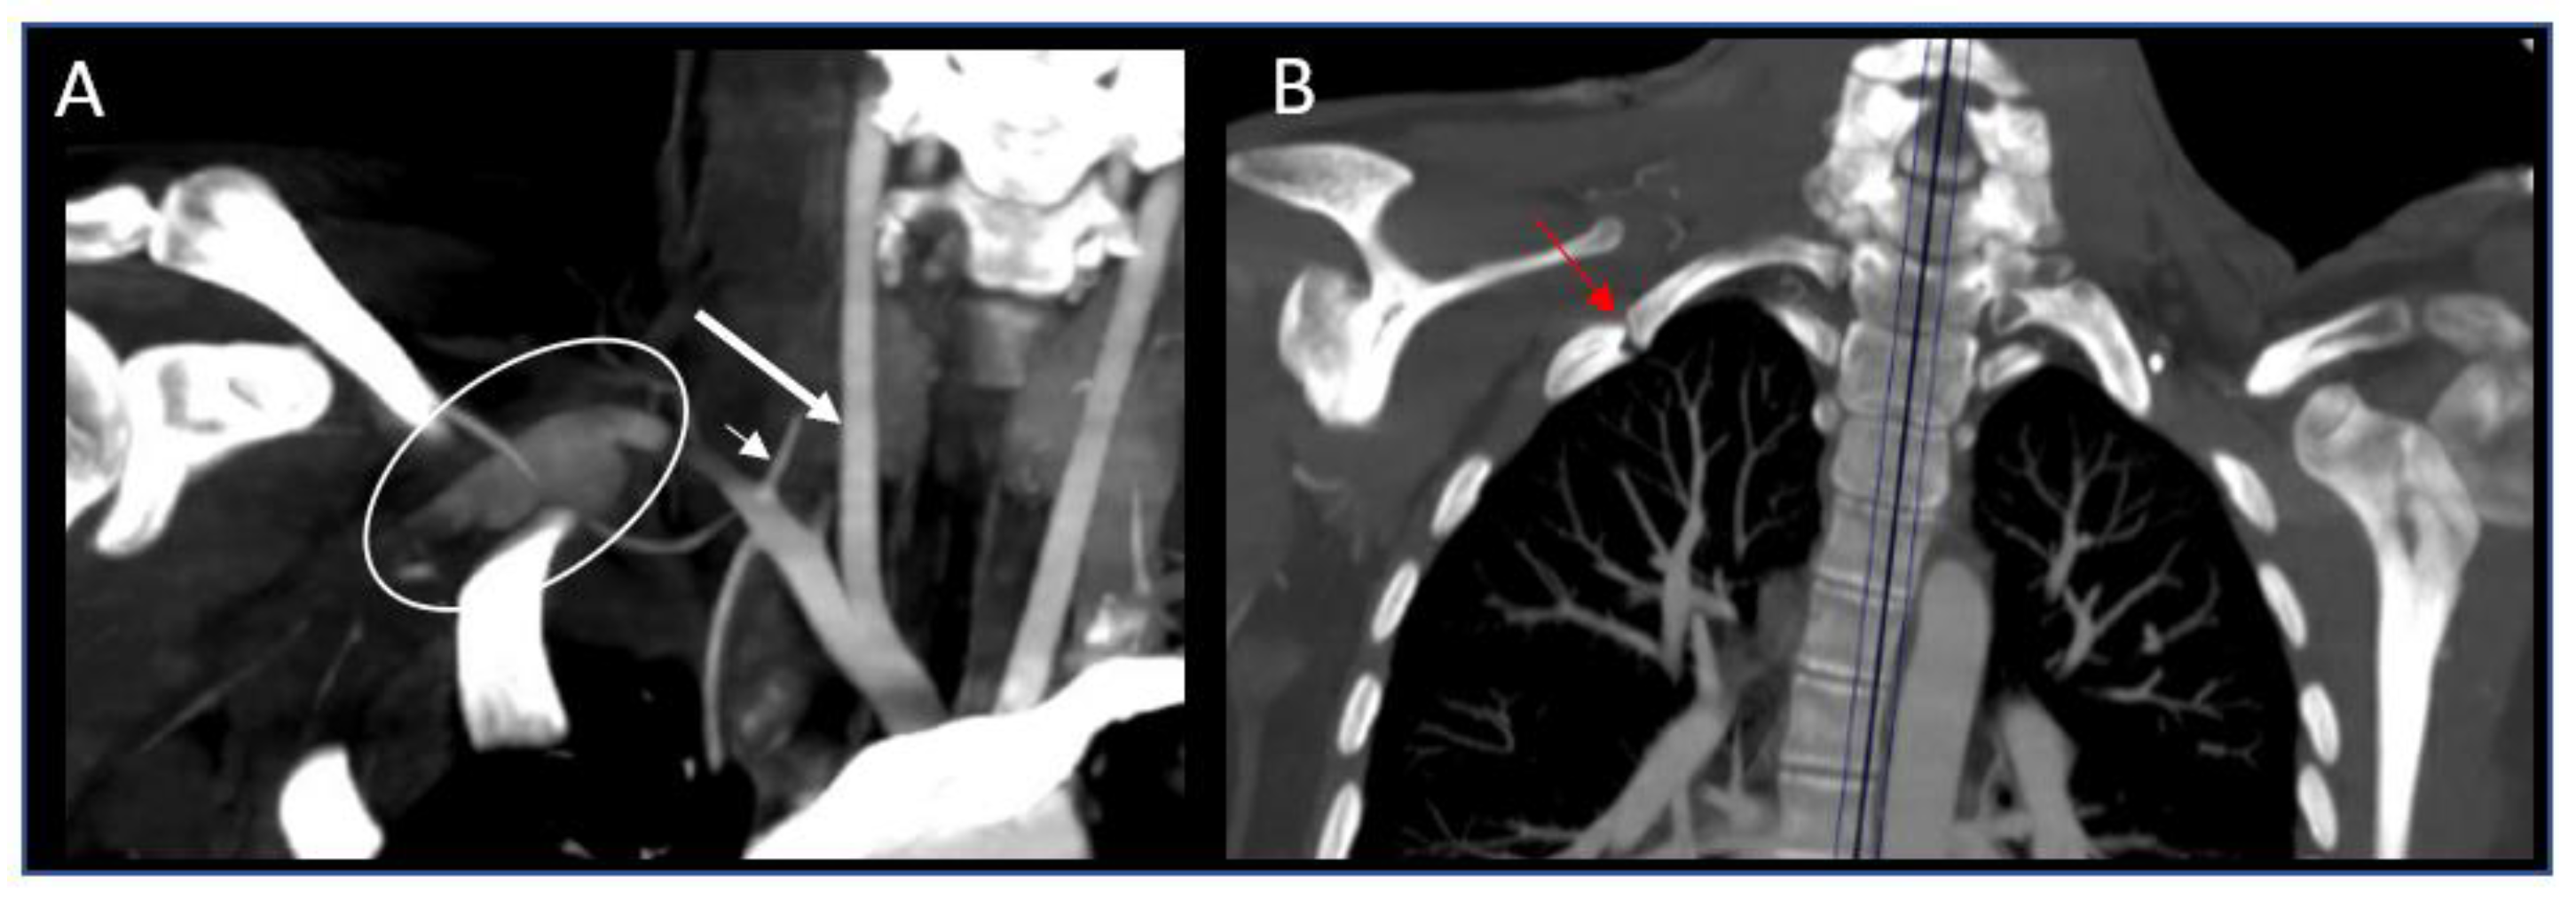

2. Case Report